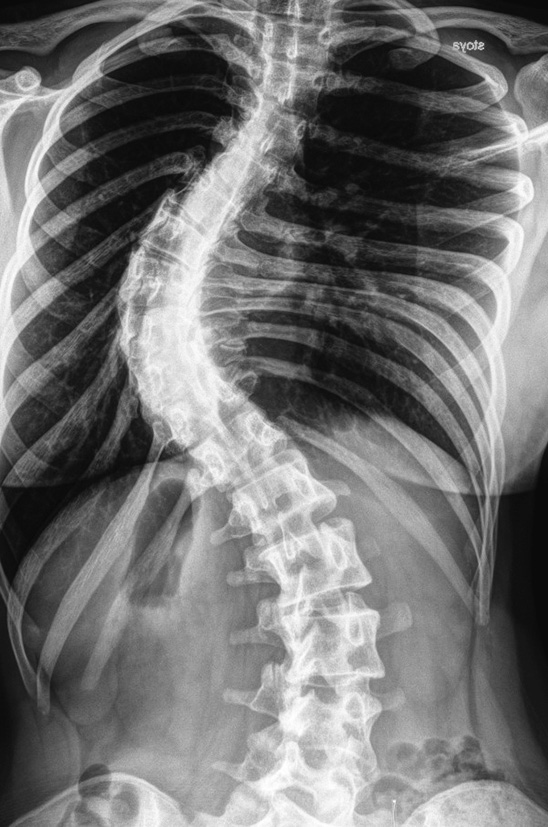

Radiographs, multispiral computed tomography (MSCT) of the spine revealed radiation pattern of severe idiopathic scoliosis of the thoracic spine. The left-sided scoliotic arch Th6–Th12 of 75° according to Cobb was determined. In functional images, the scoliotic arch was rigid, corrected to a value of 70° according to Cobb. The frontal balance was physiological. Rotation and torsion of the vertebrae have secondary degenerative and dystrophic changes in the vertebral-motor segments of the thoracic and lumbar regions (most pronounced at the apices of the scoliotic arches). No areas of bone density were revealed in the spinal canal (Fig. 1, 2).

Fig. 1. X-ray of the spine in a frontal view in a standing position

Fig. 2. X-ray of the spine in a lateral view in a standing position